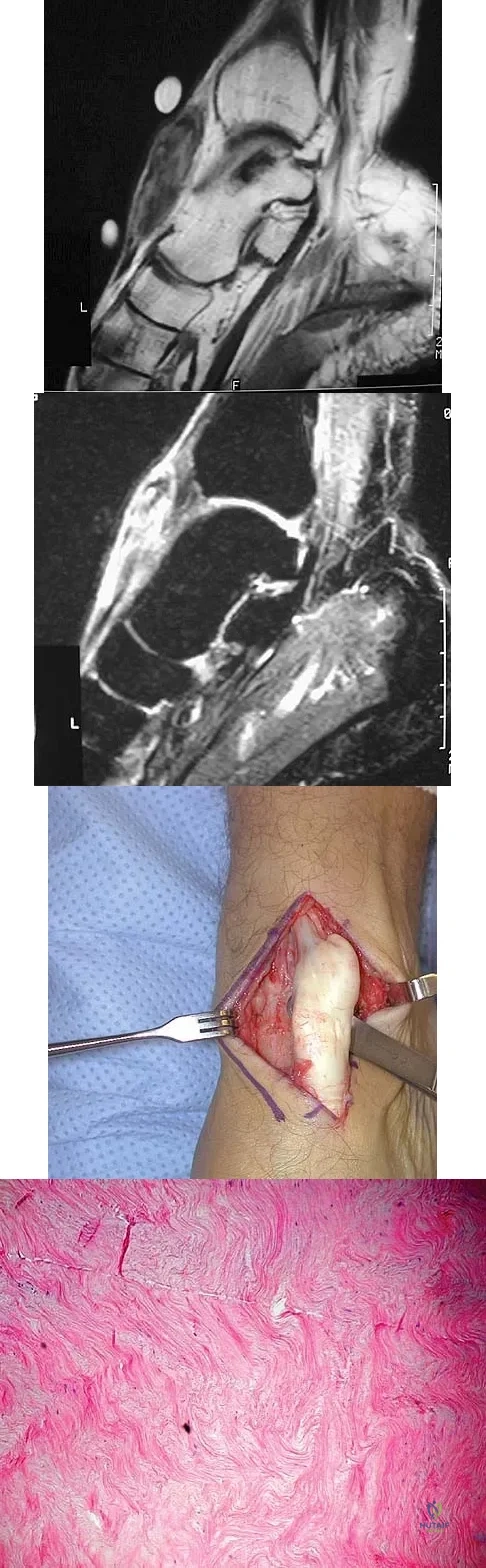

A 40-year-old man has a palpable mass over the dorsum of the ankle. He reports no history of direct trauma but notes that he sustained a laceration to the middle of his leg 6 weeks ago. Examination reveals a 4-cm x 1-cm mass. T1- and T2-weighted MRI scans are shown in Figures 12a and 12b. An intraoperative photograph and biopsy specimen are shown in Figures 12c and 12d. What is the most likely diagnosis?

A 20-year-old patient has foot pain. A radiograph and T1-weighted MRI scan are shown in Figures 8a and 8b. A biopsy specimen is shown in Figure 8c. Treatment should consist of

A 69-year-old man has a painful slow-growing lesion of the distal phalanx of his thumb. History reveals that he has had chronic osteomyelitis of the thumb for the past 12 years. The radiograph and biopsy specimens are seen in Figures 9a through 9c. Treatment should consist of